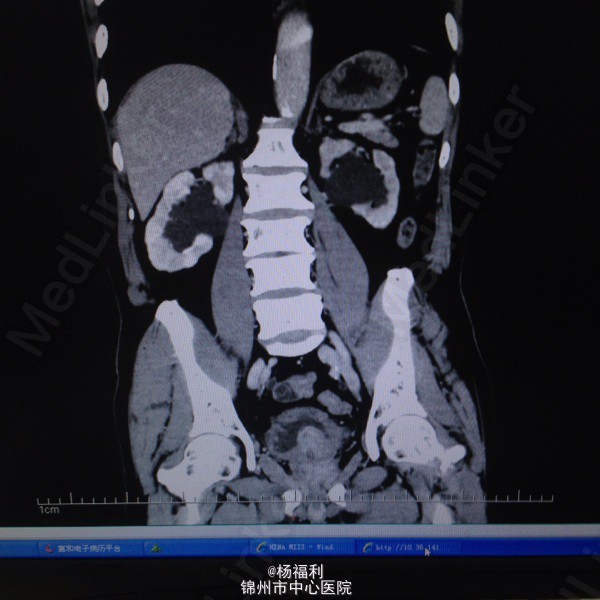

71岁男患,5年前即开始出现尿频,尿急。夜尿3-4次。排尿困难。无发热、无腰痛,无肉眼血尿。一直未与治疗。症状进行性加重。半月前患者排尿困难症状严重,尿滴沥。伴右腰部疼痛来我院就诊。

双肾区无叩击痛。双输尿管走形区无压痛,耻骨上区压痛。叩诊浊音。前列腺指诊前列腺增大,中央沟消失,质韧。未触及硬结及肿物。 彩超;双肾积水,前列腺增大突入膀胱,膀胱肌小梁形成。 ctu:前列腺增生。双侧肾盂及输尿管扩张,左肾多发小囊肿。 膀胱镜:前列腺增大突入膀胱,膀胱内多发小房小梁。 总psa:4.6ng/ml,比值:0.18。 肌酐:175umol/l。 尿常规:白细胞2+。

1、尿潴留2、前列腺增生症3、双肾及输尿管积水4、泌尿系感染。 给予患者留置尿管后择期行经尿道前列腺等离子电切术。 患者家里条件不太好,要求给予快速手术。未等肌酐及积水好转后即给予手术。